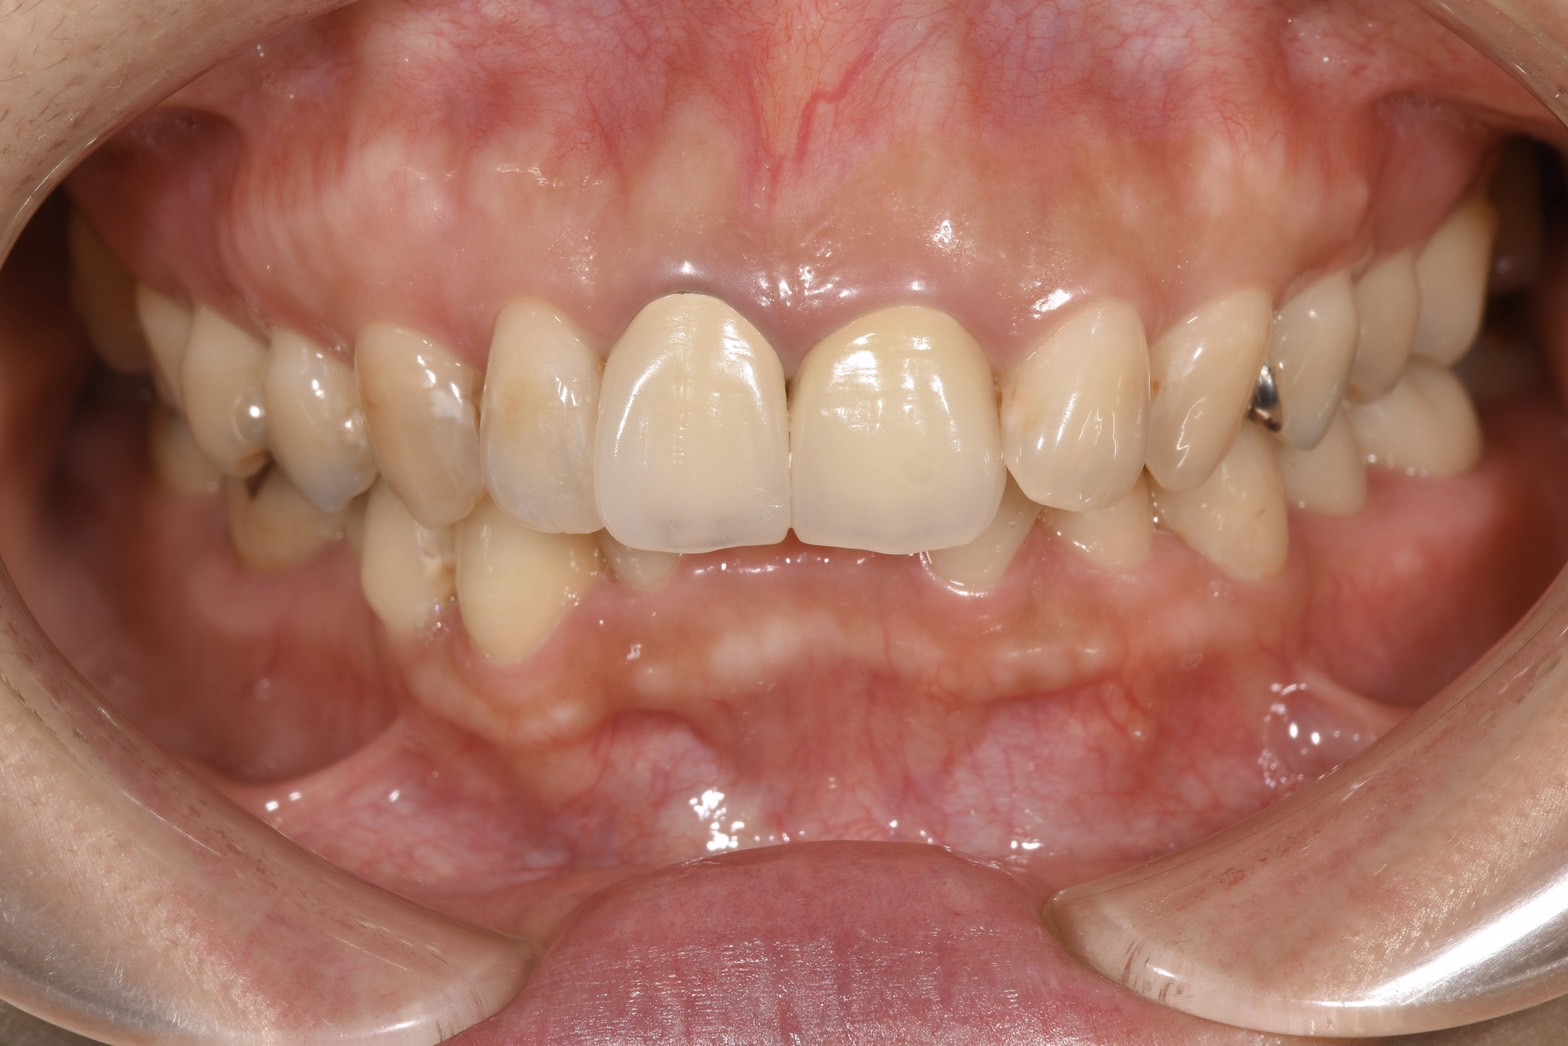

After

術後

歯肉の炎症による赤み、金属の土台による変色、天然歯との色の不調和を改善できた。